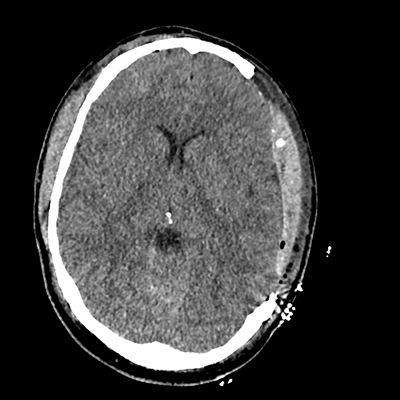

On day 5 of admission, he begins having intracranial hypertension again, spiking up to 40mmHg. You bolus with propofol and fentanyl, to no avail. You then push 30mL of 23.4% NaCl, which provides some brief improvement, allowing you to quickly get a non-contrast head CT. Unfortunately, he's now back up to 36mmHg. You review his labs, and note the following: Na 150, K 3.8, Cl 119, HCO3 18, BUN 21, Cr 0.85, glucose 136, sOsm 320.

NCHCT

NCHCT 1/20 1/20